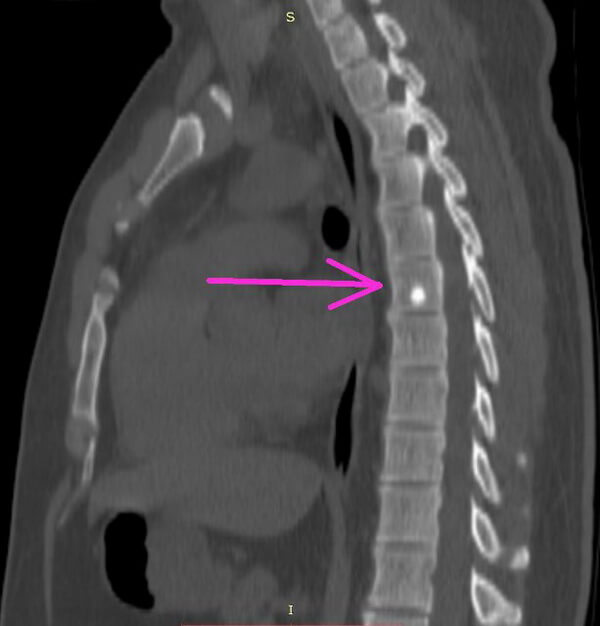

- на рентгенологических снимках позвоночника (рентгенографии), при рентгеноскопии;

- при проведении компьютерной томографии, особенно её современной модификации – цифровой (мультиспиральной) КТ;

Эностоз (костный островок) – это доброкачественное поражение кости обычно являющееся случайной находкой. Представляет собой небольшой фокус компактной губчатой кости. Его размер обычно не превышает 2 см. Состояние, при котором возникает множество костных островков, называется остеопойкилозом.

Что такое очаг эностоза?

Эностоз представляет собой округлый или овальный гомогенный очаг с признаками кортикального слоя (плотного вещества) кости. Размер обычно не превышает 1 см, но бывают гигантские образования.